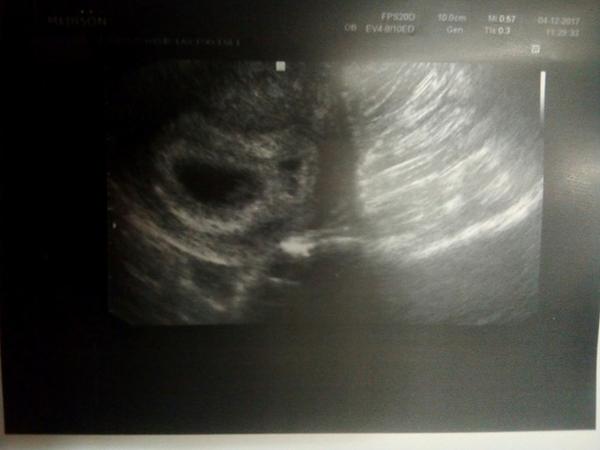

Překrásná zpráva, čekáme miminko. Testíky krásně potvrzené a hurá k dr na 1.UZ. Byl v 5+4tt kdy byla vidět jedna dutinka (prázdná) a doma jsem si na fotce všimla ještě jedné miniaturní dutinečky o které dr nic neříkal.

Další kontrola v 7+2tt. Na uz krásná dutinka s fazolkou a srdíčkem. Nad tím byla další dutinka, ale o doooost menší, ale též měla embryo. Jenže dr se o ni ani nezmínil a až když jsem se zeptala tak hned odpověděl, že dvojčátko, které se nevyvíjí, tudíž syndrom mizejícího dvojčete. Takže šok v šoku. Nic víc neřešil. Mám průkazku, tam jen zmínka o jednom.

Ale nechápu, jak když to druhé též vyrostlo a to snad i o víc, jak první, tak jak může být nevyvíjející?? Hlavně jsem i četla, že jsou případy, kdy je druhé mimi mladší o několik dní či i týdnů.

Přidávám i fotečky a moooooc prosím o vysvětlení, uklidnění či cokoliv, co mi to pomůže pochopit.

@pitryludvikova no právě že stejná nebyla. Od toho prvního UZ se ohromně zvětšila, jen prozatím neměla srdíčko. Jen mne zaráží, že má malý váček, ale jinak je stejně velké ... fakt to mám strašně pomotané. Kdyby nerostlo neřeknu, ale vyrostlo opravdu hodně... ta kvalita je špatná, pak dopošlu lepší

@tynka07 tak to tezko rict, je mozne ze je jen mladsi treba o 14 dnu...